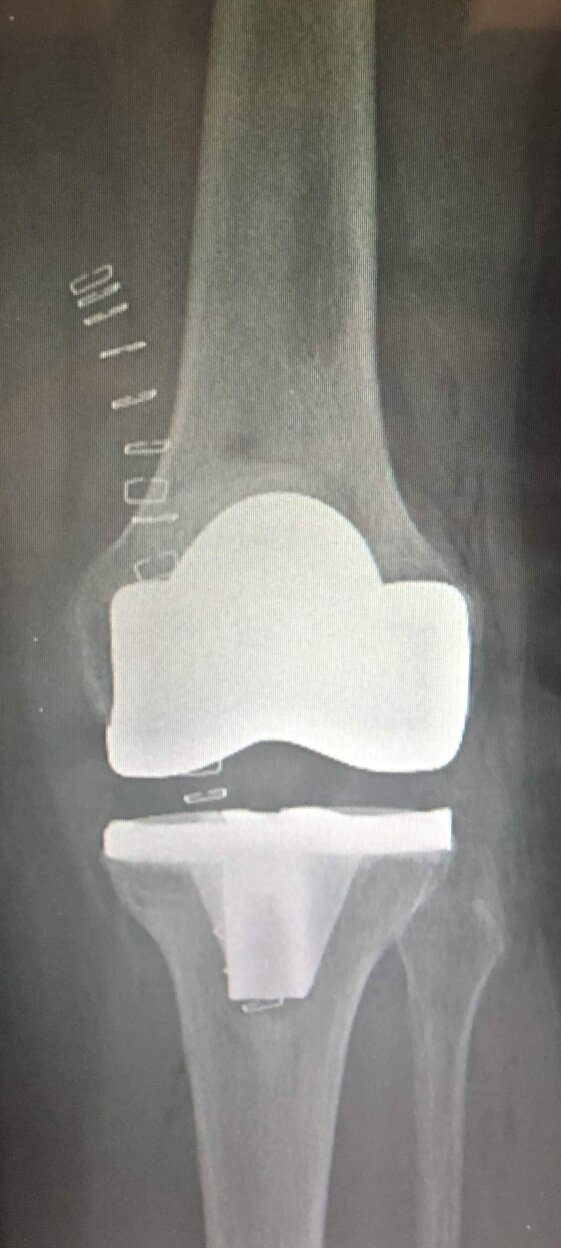

A sinistra radiografie pre-operatorie il AP e LL che evidenziano una grave gonartrosi diffusa con presenza di osteofiti periarticolari e deformità associata (ginocchio varo).

A destra radiografia post-operatoria in AP e LL di intervento chirurgico di artroprotesi di ginocchio cementata, unico trattamento possibile con pz che presentava dolore continuo e zoppia. Ho utilizzato una protesi con risparmio del legamento crociato posteriore (CR) chiamata Persona proprio perché altamente anatomica, cioè molto rispettosa dell’anatomia del ginocchio del singolo paziente. La paziente presentava un sovrappeso per cui ho optato per una componente protesica tibiale con un fittone più lungo proprio per avere più resistenza